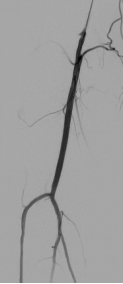

★ 病例 1

图:DA 造影+通过病变

图:IVUS确认

图:Hawk Plus 切除斑块

图:IN.PACT DCB 6-250 扩张,最终造影